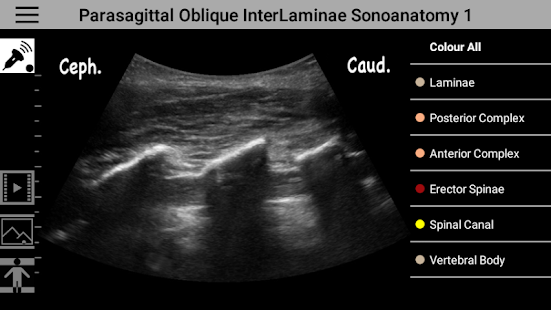

AnSo is designed by anesthesiologists for anesthesiologists. Have this resource in your pocket to help you identify anatomical structures with ultrasound. AnSo allows the user to identify sonoanatomy by placing single or multiple color overlays on and off ultrasound images. AnSo is for more than just a regional anesthesia. It includes other perioperative uses of ultrasound, such as: